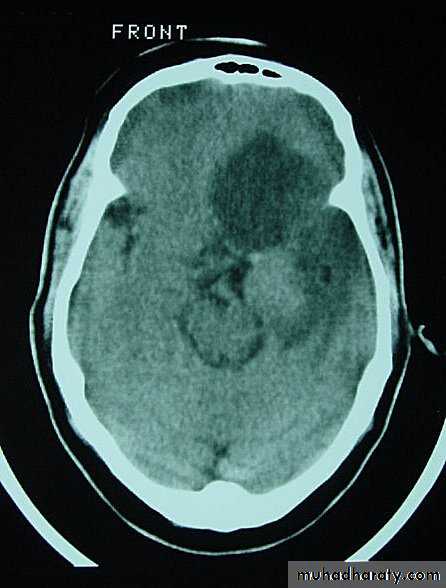

Metastatic Brain Tumours

Neurosurgery

Metastatic Brain Tumours Pre contrast CT

Metastatic Brain Tumours Post contrast CT